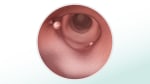

• Tests that look inside the colon: Every 5 to 10 years for colonoscopy or every 5 years for sigmoidoscopy and CT colonography. (If you do the FIT test every year, you can get a sigmoidoscopy every 10 years.)